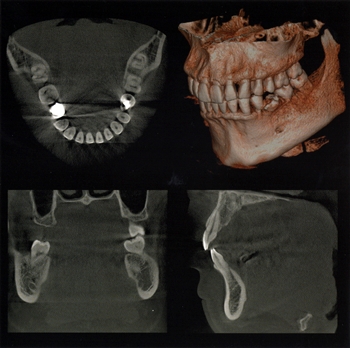

歯と歯の周りの状態を詳しく知り、正確な診断と安全確実な治療のために歯科用CTを導入。あごの骨の立体的な形態や、神経の位置把握、さらに骨密度の比較などを行います。

今ではインプラント治療の診断にはCTは必須のものとなっていますが、インプラントに限らず、根管治療(歯の根の治療)や、歯周病治療のより適切な診断・治療にも大きく役立っています。

- ・わかりやすい立体(3D)画像で症状をご説明いたします。

- ・今まで見えなかった歯の中や骨の中まで立体的に見ることができます。